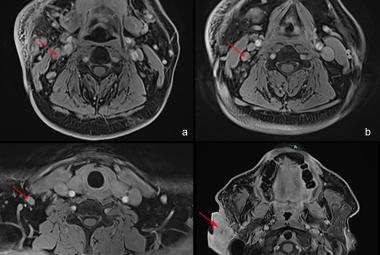

Superior mesenteric artery syndrome (SMAS), or Wilkie’s syndrome, is a rare cause of duodenal obstruction, whereby the duodenum is compressed between the superior mesenteric artery (SMA) and abdominal aorta (AA) due to a loss of mesenteric fat pad. This condition is associated with high morbidity and mortality, particularly if the diagnosis is delayed, leading to complications such as gastric perforation or aspiration pneumonia. A 14-year-old boy with an underlying severe autism spectrum disorder, complained of a two-day history of abdominal pain and vomiting, suggestive of gastric outlet obstruction, leading to hyperlactatemia and metabolic acidosis. An immediate contrast-enhanced computerised tomography revealed a significant dilatation of the lower esophagus until the D3 segment of the duodenum, narrowing of the aortomesenteric angle, and shortening of the aortomesenteric distance, findings suggestively of duodenal obstruction secondary to SMAS. However, patient subsequently developed persistent vomiting leading to aspiration pneumonia. He rapidly deteriorated into septic shock with multiorgan failure, ultimately leading to his death. This case report aimed to highlight the challenges in diagnosing and managing SMAS particularly in autistic children as they may have difficulty communicating their distress, and there is a potential of rapid deterioration that requires prompt escalation of care.